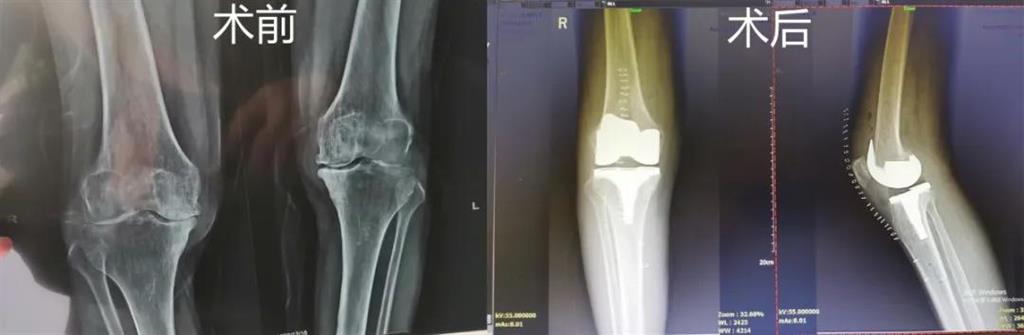

和平國(guó)際醫(yī)院副院長(zhǎng)、骨科中心主任劉丹在診斷后發(fā)現(xiàn),老人雙側(cè)膝關(guān)節(jié)患有骨性關(guān)節(jié)炎,右側(cè)膝關(guān)節(jié)較為嚴(yán)重,而且關(guān)節(jié)磨損嚴(yán)重關(guān)節(jié)間隙基本消失。

經(jīng)過進(jìn)一步檢查后,劉丹帶領(lǐng)團(tuán)隊(duì)在計(jì)算機(jī)導(dǎo)航系統(tǒng)的輔助下,為老人實(shí)施了右側(cè)全膝關(guān)節(jié)置換手術(shù)。術(shù)中出血明顯減少,術(shù)后疼痛腫脹等反應(yīng)輕微,畸形矯正力線恢復(fù)理想,而且功能恢復(fù)快速,術(shù)后四天就可以下地行走。

據(jù)劉丹主任介紹,計(jì)算機(jī)導(dǎo)航膝關(guān)節(jié)置換術(shù)可以避免打開股骨髓腔,從而明顯減小手術(shù)創(chuàng)傷,減少術(shù)中出血,能夠更精準(zhǔn)地從三維角度調(diào)整手術(shù)截骨方向,恢復(fù)肢體對(duì)線,并能進(jìn)行精確的軟組織平衡,從而使患者獲得良好的術(shù)后功能恢復(fù)。